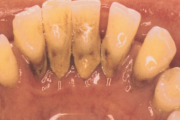

Krooniline parodontiit

Krooniline parodontiit on mikroobide poolt põhjustatud hammaste tugikudede põletik, mille tulemusena tekib progresseeruv alveolaarluu (nähtav röntgenograamil) ja periodontaalligamendi destruktsioon, igemetaskute moodustumine, igeme retsessioon või mõlemad kahjustused kombineeritult. Loe edasi »

- igemed veritsevad (19)

- igemed punetavad (21)

- igemed on tursunud/vohavad (17)

- igemepiir on taandunud (3)

- igemepealne hambakivi (5)

- igemealune hambakivi (4)